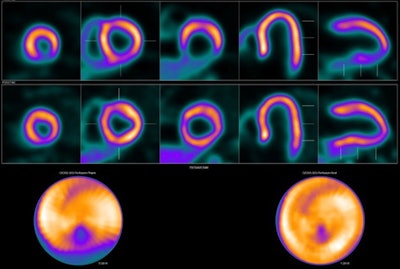

Out of 604 participants in the trial, 298 (51.6%) were classified as obese, with a mean body mass index (BMI) of 35.8 kg/m2. Patients had undergone one-day rest-stress F-18 flurpiridaz PET or one- or two-day rest-stress Tc-99m-SPECT MPI exams. Images were read by three experts, with the sensitivity and specificity of the two approaches then compared in the obese group.

Performance by modality in obese patients | ||

Tc-99m SPECT MPI | F-18 flurpiridaz PET | |

Sensitivity | 63.8% | 80.3% |

Specificity | 61.7% | 63.8% |

Radiation exposure | 12.4 mSv | 6.2 mSv |